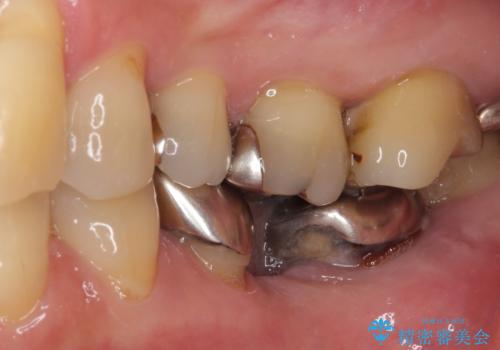

- 前歯の歯肉の腫れを気にして来院された患者様です。

前歯のみならず、奥歯の銀歯や下顎前歯のデコボコなど、色々と気になる部分を治したいとのことでした。

前歯は抜歯が必要であったので、抜歯を行い、その後歯肉移植をおこなった上でオールセラミックブリッジによる補綴治療を行うこととしました。

下顎と上顎臼歯部については矯正治療を行い、奥歯の欠損部位はオールセラミックブリッジを、その他の銀歯はセラミックインレーなどにより治療を行うこととしました。